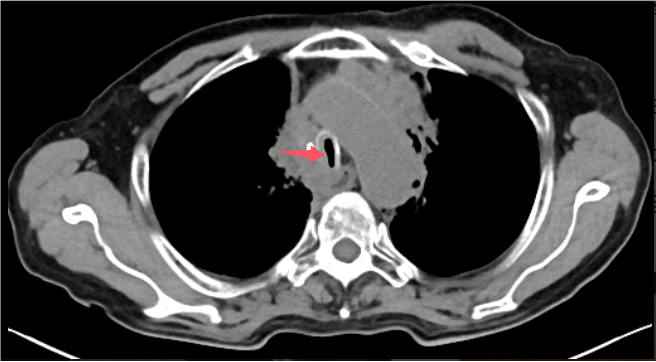

72歲的程爺爺,因“確診肺癌5年余,咳嗽、咳痰伴間斷咯血兩個月”入院。檢查發現其左肺鱗癌已進展至Ⅳ期,腫瘤侵犯導致氣管中下段及隆突區域形成約4.5厘米的極重度狹窄,嚴重影響呼吸功能,同時患者合并心房顫動、心包積液等多系統并發癥,治療難度極高。

術前胸部CT見患者氣道狹窄,呈一縫隙

術后復查胸部CT見氣道通暢